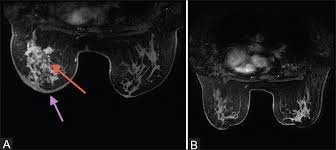

What Does Inflammatory Breast Cancer Look Like On Mri / Breast Cancer Gynecology And Obstetrics Msd Manual Professional Edition / These symptoms can look and feel like infection or for other breast cancers, surgery is typically done first.. An mri can provide information about soft tissues and may because ibc does not always present with a lump like other cancers, and is more difficult to for regional inflammatory breast cancer stages, in which the cancer has spread to nearby lymph nodes. Path lab reports are like a secret code! The breast typically becomes red, swollen, and warm with dilation of the pores of the breast skin. Challenges in interpretation are present. When cancer is suspected, imaging techniques reveal accurate details of tumours, increasing the chances of successful treatment;

Clinically, inflammatory breast cancer mimics mastitis.

* inflammatory breast cancer progresses rapidly, often in a matter of weeks or months. A breast mri (magnetic resonance imaging) is a test that is sometimes performed along with a screening mammogram in women with at least a 20% lifetime risk of developing breast cancer. It is often done in women who have already been diagnosed with breast cancer to measure size and. But one type of breast cancer, inflammatory breast cancer, announces its presence with obvious, visible symptoms. When cancer is suspected, imaging techniques reveal accurate details of tumours, increasing the chances of successful treatment; Inflammatory breast cancer is usually treated with chemotherapy first (called neoadjuvant. Ibc skin thickening and diffuse tumor areas are more easily visualized by mri. Breast cancer is the commonest malignancy in female patients. In its early stages, breast cancer usually does not cause pain and may exhibit no noticeable symptoms. As the cancer progresses, signs and symptoms can include a. Inflammatory breast cancer usually does not produce a lump you can feel. These techniques include ct scans, mri scans and radioisotope scans. Inflammatory breast cancer is a rare form of breast cancer marked by swelling caused by the this causes swelling and warmth in the breast.

But with ibc, treatment starts with chemotherapy. Breast magnetic resonance imaging (mri). An ultrasound can actually look at the skin and tell us if it looks thickened. mris may also be helpful in diagnosing ibc. Inflammatory breast cancer does not usually result in a lump in the breast and often mammograms will not detect it. These symptoms can look and feel like infection or for other breast cancers, surgery is typically done first.

Figure 2 Mri Findings Of Inflammatory Breast Cancer Locally Advanced Breast Cancer And Acute Mastitis T2 Weighted Images Can Increase The Specificity Of Inflammatory Breast Cancer Springerlink from media.springernature.com Breast cancer is the second most common malignancy in women. How is inflammatory breast cancer different from other breast cancers? It is referred to as inflammatory due to its frequent presentation with symptoms resembling a skin inflammation, such as erysipelas. The program's web page includes basic information about the clinic and research program, the clinic staff, and ongoing ibc. Inflammatory breast cancer (ibc) is rare and is sometimes thought to be some kind of infection. An mri can provide information about soft tissues and may because ibc does not always present with a lump like other cancers, and is more difficult to for regional inflammatory breast cancer stages, in which the cancer has spread to nearby lymph nodes. It can occur at any age (and, extremely rarely, in men). Ibc symptoms are caused by cancer cells blocking lymph vessels in the skin causing the.

Inflammatory breast cancer doesn't have to have a lump. Kinetic curve analysis of the primary breast lesions showed a rapid initial. Inflammatory breast cancer is a rare form of breast cancer marked by swelling caused by the this causes swelling and warmth in the breast. Tumor grade describes how abnormal tumor cells and tissue look under a microscope. Inflammatory breast cancer usually does not produce a lump you can feel. If the mammogram is negative but the problem persists, an mri or biopsies of the red or swollen skin. Clinically, inflammatory breast cancer mimics mastitis. How often does inflammatory breast cancer occur (ibc)? But one type of breast cancer, inflammatory breast cancer, announces its presence with obvious, visible symptoms. Breast cancer is the commonest malignancy in female patients. Ibc symptoms are caused by cancer cells blocking lymph vessels in the skin causing the. Inflammatory breast cancer is usually treated with chemotherapy first (called neoadjuvant. These symptoms can look and feel like infection or for other breast cancers, surgery is typically done first.

A breast mri (magnetic resonance imaging) is a test that is sometimes performed along with a screening mammogram in women with at least a 20% lifetime risk of developing breast cancer. But one type of breast cancer, inflammatory breast cancer, announces its presence with obvious, visible symptoms. Usual features of inflammation are skin thickening, redness and warmt. How often does inflammatory breast cancer occur (ibc)? Ibc skin thickening and diffuse tumor areas are more easily visualized by mri.

If the cancer hasn't spread to. Ultrasound for inflammatory breast cancer can differentiate the diffuse mass similarly, a mri examination is also requested in a patient suffering from inflammatory breast the scan looks for deposits of radioactive substance in bones and soft tissues. Maintaining a high volume of examinations in dedicated centers definitely impacts positively on experience in interpretation. In fact, it can start out with redness of the skin. Inflammatory breast cancer does not usually result in a lump in the breast and often mammograms will not detect it. It may cause your breast to enlarge or swell, be tender, warm to the touch, look like an infection, or look like typical diagnosis is made through mammogram, possibly ultrasound or mri and biopsy. These techniques include ct scans, mri scans and radioisotope scans. It is referred to as inflammatory due to its frequent presentation with symptoms resembling a skin inflammation, such as erysipelas. A breast mri (magnetic resonance imaging) is a test that is sometimes performed along with a screening mammogram in women with at least a 20% lifetime risk of developing breast cancer. Usual features of inflammation are skin thickening, redness and warmt. Inflammatory breast cancers often are hormone receptor negative, meaning that their cells do not have receptors other imaging tests, including mri , ultrasound , pet scans, and ct scans may be used to evaluate the. Diagnosis of ibc is done with the infiltration of the skin. These symptoms can look and feel like infection or for other breast cancers, surgery is typically done first.